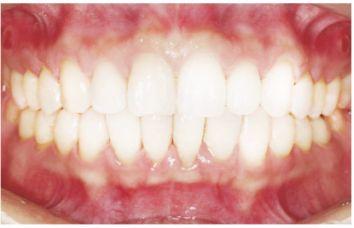

種植修復后照片

這一位老先生則選擇了All-on-4種植技術,即拔即種,上下頜分別種植4個植體就完成了全口牙齒修復,費用降低了不少,而且創(chuàng)傷小,恢復快。